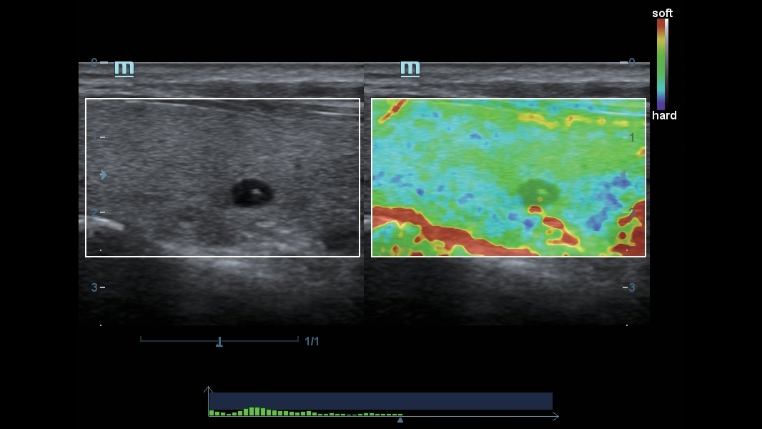

Klassieke beeldvormingstechnologie?n: verbetering van de kwaliteit voor diagnoses

DC-40 met Full HD maakt gebruik van klassieke beeldvormingstechnologie?n die van gevestigde ultrasoundsystemen zijn gemigreerd om u beelddetails van betere kwaliteit te bieden.

- iClear (beeldvormingstechnologie die spikkels reduceert)

- PSH (Phase Shift Harmonic-beeldvorming)

- iBeam: ruimtelijke beeldvormingstechnologie